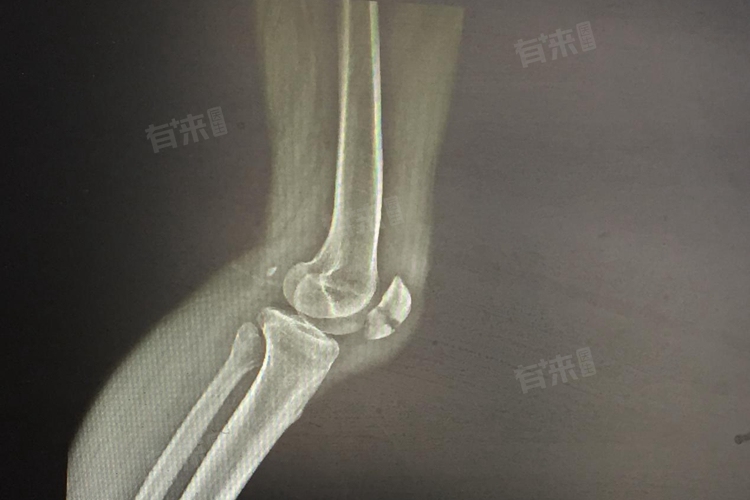

1、影像学检查:X线检查明确是否存在骨折及骨折类型,观察骨皮质连续性与关节对位情况;CT扫描对复杂骨折、隐匿性骨折有更高分辨率;MRI用于评估软组织损伤,显示肌肉、肌腱、韧带撕裂程度及关节腔内积液情况;